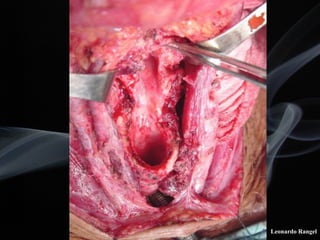

!TÉCNICA

LPSC